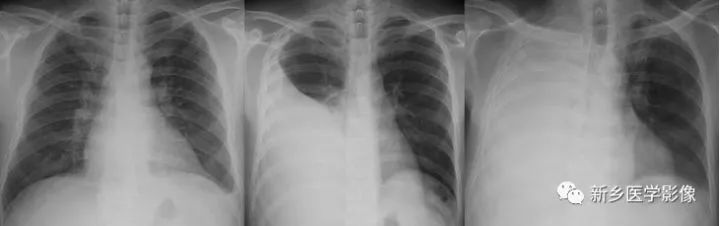

胸膜腔积液X线胸部正位片图

a. 左侧少量胸膜腔积液 b. 右侧中量胸膜腔积液 c. 右侧大量胸膜腔积液

(1)少量积液

积液上缘未达到第4前肋水平。立位时液体最先集聚于后肋膈角,此时侧位片可显示后肋膈角变钝,而正位片则显示不清。当积液量达300ml左右时,胸部正位片可见患侧肋膈角变钝。透视下可见液体随呼吸运动及体位的改变而移动,借此可同轻度胸膜增厚、粘连相鉴别。

(2)中等量积液

积液上缘超过第4前肋但尚未达到第2前肋端下缘时,为中量胸膜腔积液。站立位时,由于液体在重力作用下聚于胸腔下部,其下方肺野表现为均匀致密影,肋膈角消失。在胸腔内的负压状态以及液体表面张力等因素作用下,液体上缘表现为外高内低凹面向上的弧形影。

(3)大量积液

积液上缘超过第2前肋水平,患侧肺野致密或仅露出少量肺尖组织。纵隔向健侧移位、肋间隙增宽、膈肌下降。